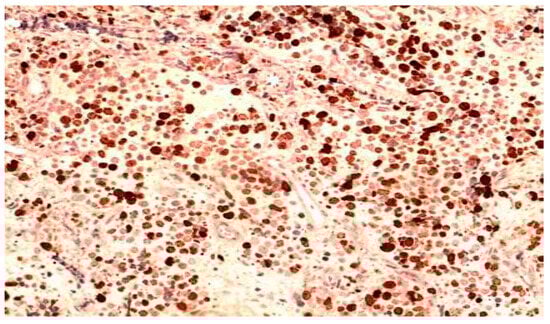

Background: Meningoencephalitis is a complex inflammatory condition of the CNS that can result in significant morbidity and mortality in critically ill adults. Accurate and timely neuromonitoring is essential for guiding management and improving outcomes. This study aimed to descriptively evaluate the prognostic value of early TCCD monitoring, particularly the pulsatility index, and its integration with conventional and perfusion MRI in patients with meningoencephalitis. Methods: We present an observational, retrospective, cohort study involving ten adult patients (median age 56 years, IQR 45.5–68.5; mean 55.9, range 35–76) with neurological syndromes caused by suspected or confirmed infectious meningoencephalitis. Etiologies included bacterial meningitis/meningoencephalitis (50%), viral meningoencephalitis (10%), neurotoxoplasmosis (10%), progressive multifocal leukoencephalopathy (10%), and undetermined origin (20%). Patients underwent TCCD and MRI within 24 h. In five cases, standard MRI sequences were acquired, while in the remaining five, perfusion imaging was performed using Arterial Spin Labelling (ASL). A favorable outcome was defined as survival with neurological recovery (Glasgow Outcome Scale > 5) at ICU discharge. Results: TCCD-derived PI provided valuable information on cerebral hemodynamics. PI values ≤ 1.25 were associated with favorable clinical outcomes and symmetrical MRI findings. Conversely, PI > 1.25 correlated with poor prognosis and often preceded MRI-detectable structural damage. When combined with ASL, PI mirrored the detected perfusion asymmetries and was associated with poor prognosis in fatal cases. Conclusions: Bedside TCCD can offer real-time assessment of cerebrovascular dynamics and, when integrated with conventional and ASL MRI, could enhance the understanding of pathophysiological processes in meningoencephalitis, supporting timely and informed decisions in neurocritical care.